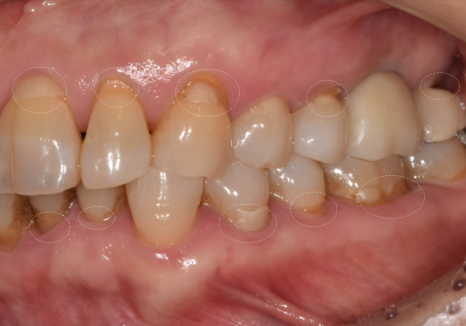

입안을 직접 살펴보니

굳이 말씀을 안 하셔도...

평소 식습관을 알 수 있을 정도였는데요~

치아의 씹는 면이

맷돌처럼 평평하게 마모되어 있었고

군데군데 작게 깨진 흔적들도 많았거든요.

251229

특히 치아와 잇몸이 만나는 목 부위가

도끼로 찍은 듯 파여있는

치경부 마모 증상도 관찰되었습니다.

강한 힘으로 음식을 씹을 때

치아가 미세하게 휘어지면서

가장 약한 목 부분이 떨어져 나가는 현상이죠.

이는 딱딱한 음식을 즐기는 분들에게

흔히 나타나는 징후들입니다.